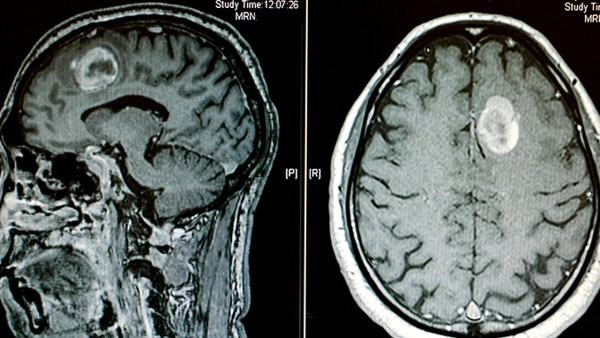

树突状细胞瘤是一种罕见的脑部肿瘤,通常发生在大脑的深部或皮层。治疗树突状细胞瘤是一个复杂而昂贵的过程,需要综合利用手术、放疗、化疗等多种治疗手段,以期达到最佳的疗效。在治疗树突状细胞瘤过程中,费用是患者和家庭普遍关注的一个问题。 树突状细胞瘤的治疗费用主要取决于多个因素,包括疾病的严重程度、所在地区的医疗资源、医疗机构的水平、医生的经验等。针对树突状细胞瘤的治疗通常需要进行手术来切除肿瘤,接着可能需要进行放疗或化疗等辅助治疗。手术费用、住院费用、药物费用、放疗费用等都将构成治疗费用的一部分。 在美国,树突状细胞瘤的治疗费用通常非常高昂。根据患者的具体病情和治疗方案不同,治疗费用可能会在数万美元到数十万美元之间波动。对于一些需要长期放疗或化疗的患者来说,治疗费用会更加昂贵。此外,随着医疗技术和治疗方法的不断进步,个别患者可能还需要接受更加昂贵的个性化治疗,进一步增加了治疗费用的负担。 针对高昂的治疗费用,患者和家庭可以通过不同的途径来寻找帮助和支持。一些医疗机构或基金会可能提供资金支持或者援助计划,协助患者支付部分医疗费用。患者也可以考虑购买医疗保险,以减轻治疗费用的压力。此外,一些社会组织和慈善机构也可能提供一定程度的经济援助。 在面对树突状细胞瘤的治疗费用时,患者和家庭不仅需要关注治疗本身的效果,还需要考虑如何有效管理治疗费用,避免因为经济负担过重而影响治疗进程。同时,政府、医疗机构和社会各界也应该共同努力,为患者提供更多的经济援助和支持,帮助他们尽快恢复健康。